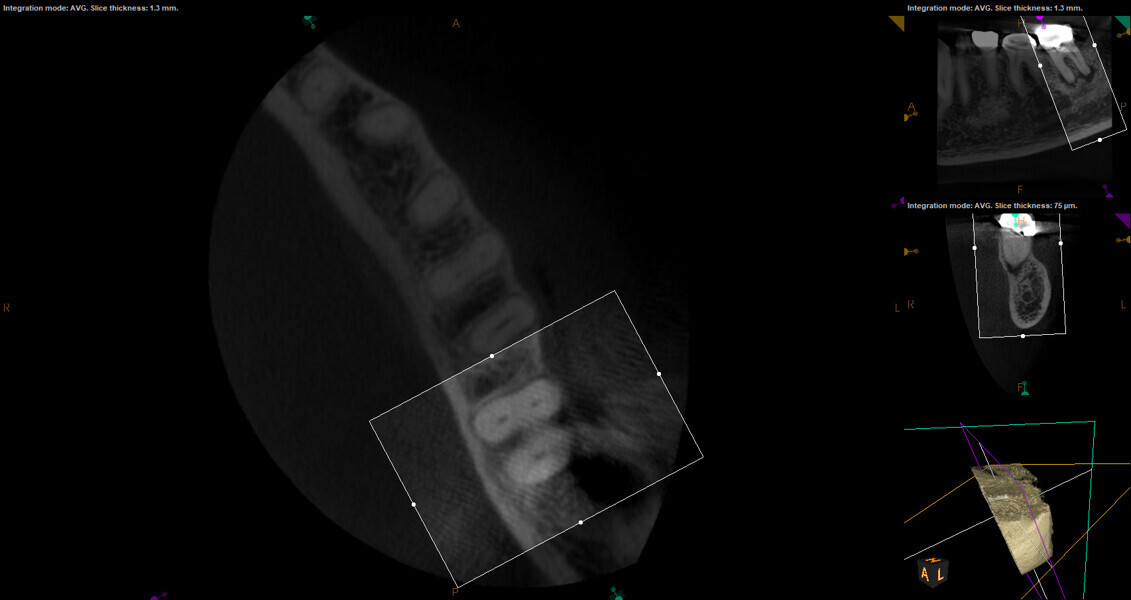

Fig. 17a: Case assisted with CBCT to determine anatomy pre-operatively. Note the multiple cross sections moving apically and the correlation to the 2-D view. Note also the conservative taper in relation to the root width. (Courtesy of Dr. Brett Gilbert)

Fig. 17b: Case assisted with CBCT to determine anatomy pre-operatively. Note the multiple cross sections moving apically and the correlation to the 2-D view. Note also the conservative taper in relation to the root width. (Courtesy of Dr. Brett Gilbert)

Fig. 17c: Case assisted with CBCT to determine anatomy pre-operatively. Note the multiple cross sections moving apically and the correlation to the 2-D view. Note also the conservative taper in relation to the root width. (Courtesy of Dr. Brett Gilbert)

Fig. 17d: Case assisted with CBCT to determine anatomy pre-operatively. Note the multiple cross sections moving apically and the correlation to the 2-D view. Note also the conservative taper in relation to the root width. (Courtesy of Dr. Brett Gilbert)

Fig. 17e: Case assisted with CBCT to determine anatomy pre-operatively. Note the multiple cross sections moving apically and the correlation to the 2-D view. Note also the conservative taper in relation to the root width. (Courtesy of Dr. Brett Gilbert)

Fig. 17f: Case assisted with CBCT to determine anatomy pre-operatively. Note the multiple cross sections moving apically and the correlation to the 2-D view. Note also the conservative taper in relation to the root width. (Courtesy of Dr. Brett Gilbert)